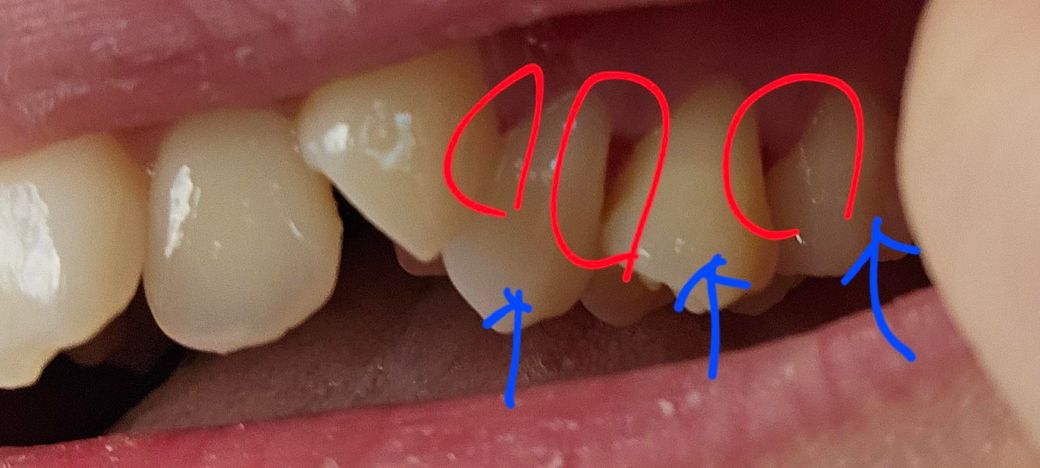

제가 치경부마모증으로 오른쪽 위쪽 어금니 3개를 레진치료를 6일전에 받았습니다.

그런데 어제 레진한 부위에 고기낀 느낌이 나서 치실을 했더니 고기찌꺼기와 투명한 껍질같은게(이게 뭔지 모르겠음) 같이 나왔습니다. 근데 여기서 문제는 치아와 치아 사이간 공간이 커져서 레진이 떨어지거나 까진 것은 아닌지 의심이 되는데. 오늘 병원가서 확인하니 의사쌤이 레진이 떨어진것은 아니라고 하셨습니다.

근데 레진이 까진것이 아니고서야 이렇게까지 이 사이 공간이 커질수가 있나요?

맨 아래 사진이 지금 치아입니다ㅠㅜ